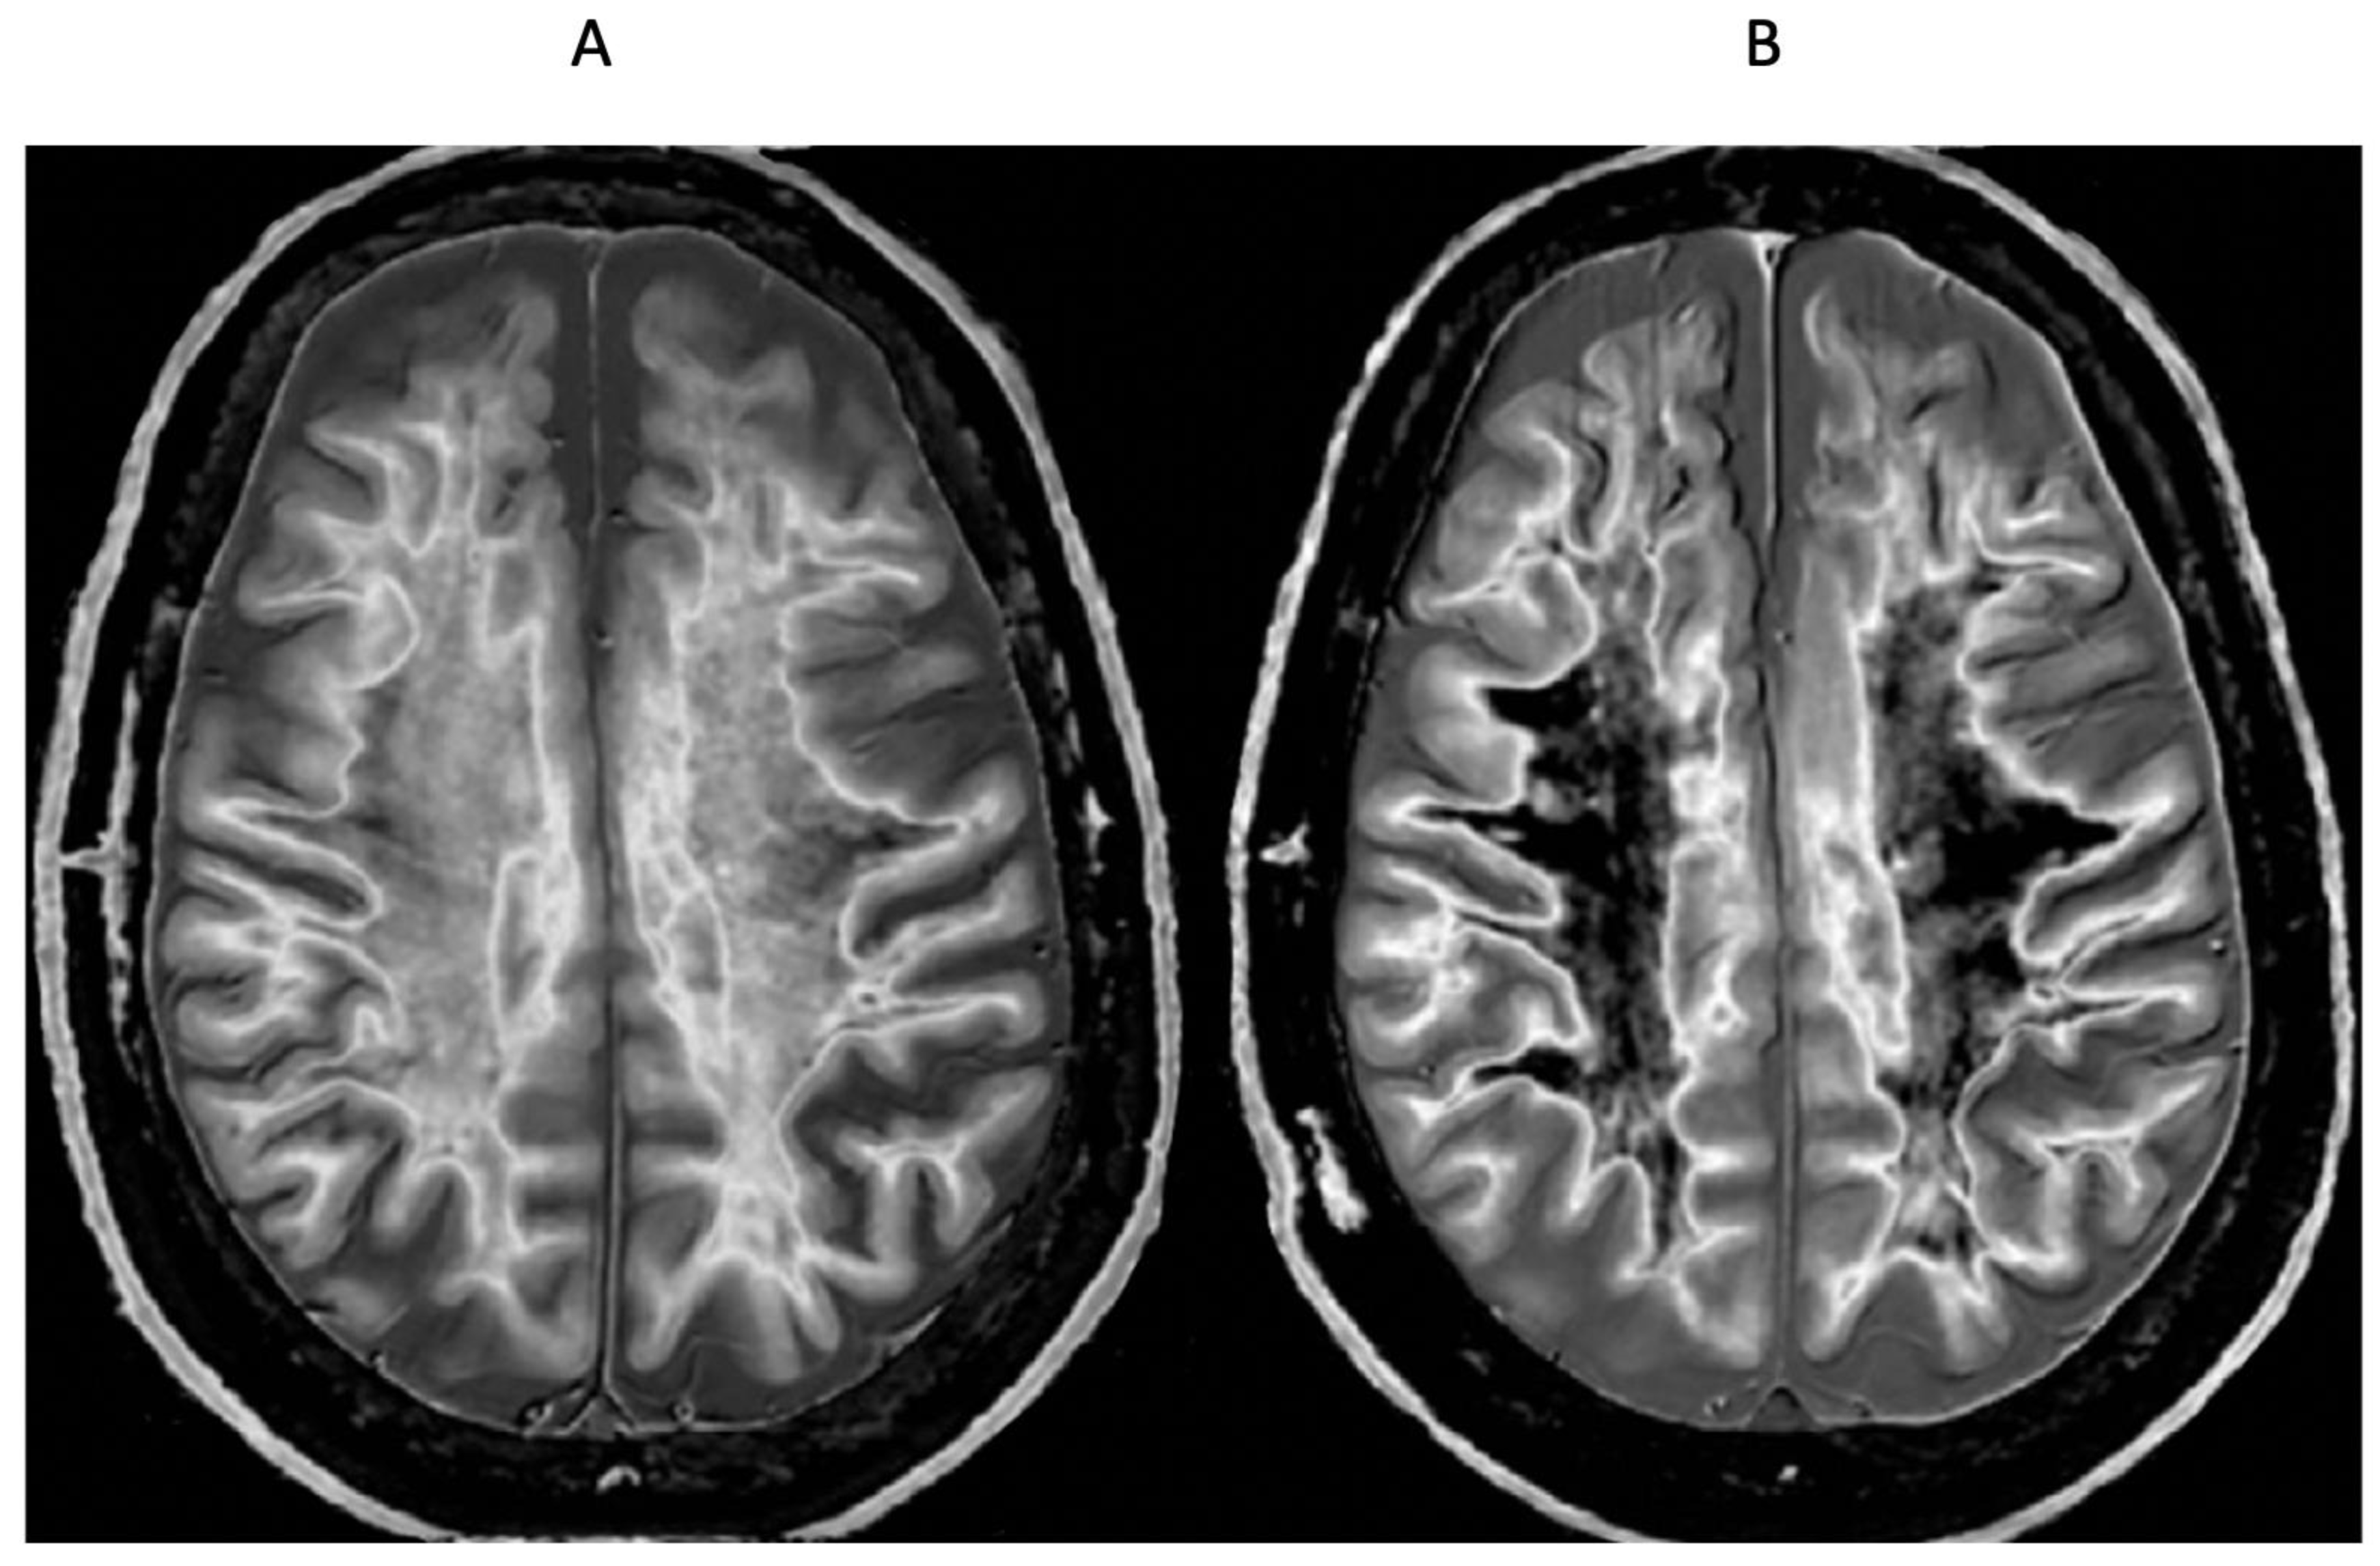

Figure 13.

Normal control (A) and patient with mTBI (B) showing a whiteout sign and grayout signs (narrow mD dSIR [T1-BLAIR] images). The normal control shows the heads of the caudate nuclei with higher signal than the adjacent CSF. Contrast is also seen between the cortex and CSF. In (B), the patient shows a whiteout sign. There are grayout signs in the thalami and putamina. In addition, contrast between the heads of the caudate nuclei and CSF is reduced and there is little or no contrast between cortex and CSF which are isointense. These are also grayout signs. No abnormality was seen on the T2-FLAIR images in the normal control or patient.